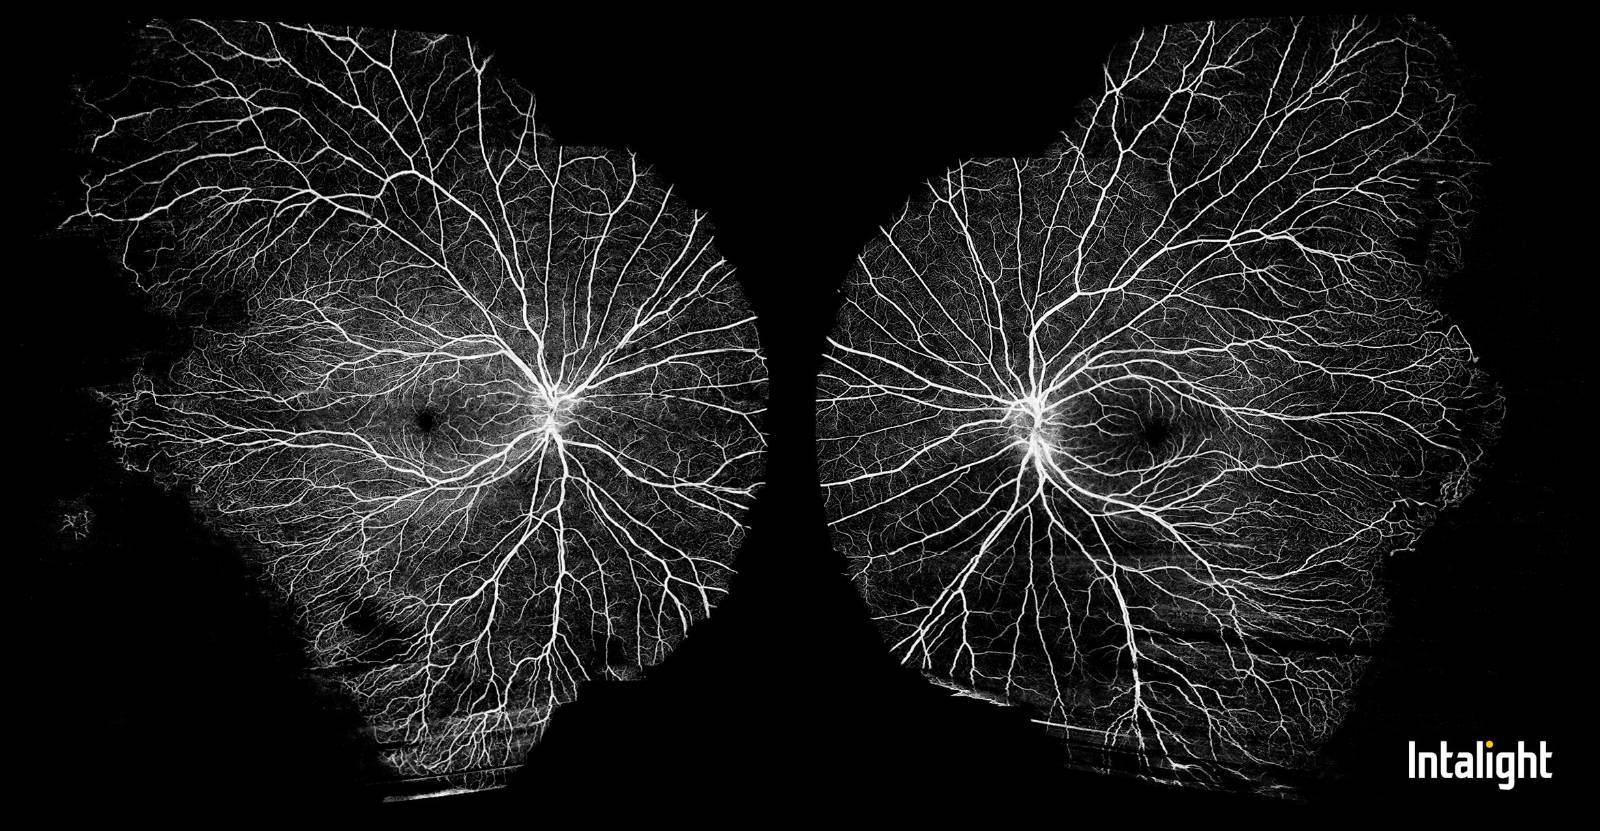

Familiárna exudatívna vitreoretinopatia

Zriedkavé dedičné vitreoretinálne ochorenie Criswick Schepens (FEVR - Familiárna exudatívna vitreoretinopatia).